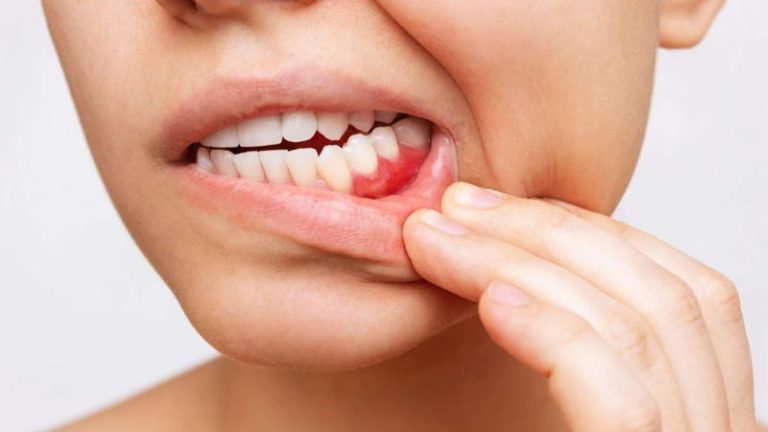

- تورم: تورم در لثه اطراف دندان (شبیه به یک جوش) یا تورم در صورت، گونه ها و غدد لنفاوی زیر فک، نشانه گسترش عفونت است.

دوران بارداری نیز یک دوره حساس است. تغییرات هورمونی در این دوران می تواند لثه ها را مستعد التهاب و عفونت کند. عفونت دندان درمان نشده در دوران بارداری می تواند خطر عوارضی مانند زایمان زودرس یا تولد نوزاد با وزن کم را افزایش دهد. درمان های دندانپزشکی ضروری مانند درمان ریشه در دوران بارداری ایمن هستند و برای جلوگیری از گسترش عفونت باید انجام شوند. خونریزی لثه در بارداری باید جدی گرفته شده و توسط دندانپزشک بررسی شود.